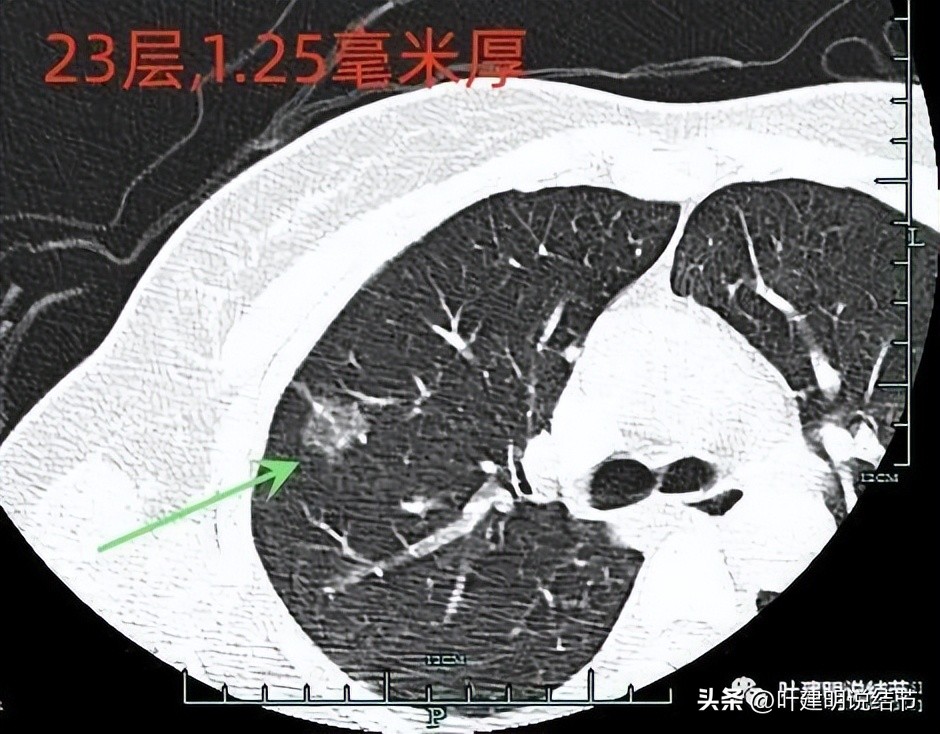

上图示病灶1的定位,红色箭头示病灶1,绿色箭头示定位医用胶。

上两图示病灶2的定位:红色箭头示病灶2,绿色箭头示医用胶。层厚1.25毫米,两者相差5层,也就是说上下相差6.25毫米,术中见到医用胶后,病灶在其下方6.25毫米。